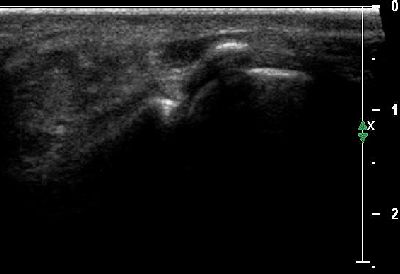

Modifiche anatomiche

Base falange prossimale Modifiche anatomiche base falange prossimale

Sesamoidi Modifiche anatomiche sesamoidi